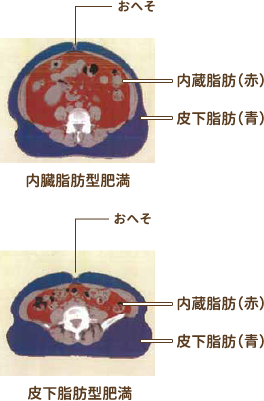

⑲内臓脂肪CT

CTで体脂肪面積を測定し、内臓脂肪型肥満を見分けるのに役立ちます。体脂肪は内臓脂肪と皮下脂肪に分類されますが、内臓脂肪の過剰な蓄積は、血糖・中性脂肪・血圧の上昇など様々な形で血管を傷つけ、動脈硬化を引き起こす原因となります。